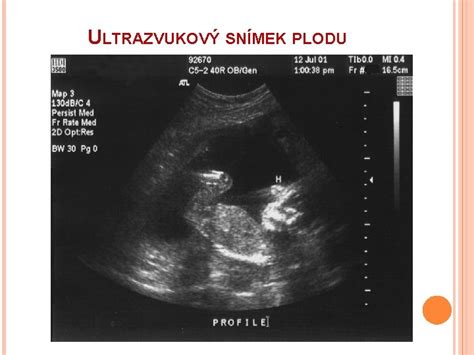

V 11. týždni tehotenstva sa vaše bábätko oficiálne považuje za plod, nakoľko fáza embrya je dokončená. Meria 40-54 mm (CRL) a váži 7-10 gramov. O chvíľu končí kritické vývojové obdobie a čaká ho fáza rapídneho rastu. Doteraz srdiečko bábätka tĺklo 10 miliónov-krát a teraz je už rozdelené na štyri časti. Do tohto týždňa sa genitálie chlapčeka a dievčatka podobali, odteraz sa začnú vývojom odlišovať. Viečka sa uzavreli a otvárať sa začnú až po 24. týždni. Telo sa napriamuje, pankreas začína tvoriť inzulín a v pečeni sa začínajú tvoriť červené krvinky. Hlava tvorí polovicu dĺžky tela.

Mozog už vysiela signály do svalov, takže bábo kope, vystiera sa a pomaly začína cvičiť dýchací a prehĺtací reflex. Na hlave a celom tele sa formujú vlasové folikuly. Sformovali sa pery a nos má otvorené priechody. Zlučujú sa kosti podnebia a na mieste je jazyk. Bránica je silnejšia - dieťa štikúta. Formujú sa lôžka na nechty a základy trvalých zúbkov. Viditeľné sú bradavky na hrudníku. Na nohách a rukách sa oddeľujú prsty. Kosti pevnejú ukladaním vápnika. Vyvíjajú sa cievy viditeľné pod tenkou vrstvou pokožky. Obličky začínajú tvoriť moč. Črevá sa vyvíjajú a časť je v pupočnej šnúre. Na UTZ vidno rastúci krk, ktorý oddelí hlavičku od telíčka.

V týchto týždňoch vás čaká prvý prenatálny skríning. Ak už máte presne určený termín, no tento týždeň vám vyšla poradňa, zrejme vám spravia klasické vyšetrenia - ako hmotnostný prírastok, zmeranie tlaku krvi, vyšetrenie moču na prítomnosť bielkovín. Ultrazvukom vám skontrolujú aktivitu plodu a vypočujete si tlkot srdca (ak vám ešte nerobili).